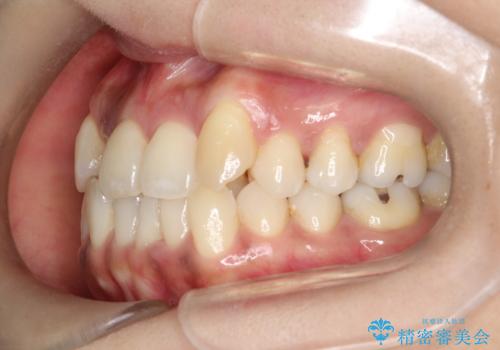

- 治療計画

- 全体のがたつきを主訴に来院されました。4番目の歯を4本抜歯も検討しましたが、口元が下がりすぎてしまうリスクと2番目の転位うが著しく並べるのにかかる期間を考慮し、変則的な抜歯をし、並べる計画を立てました。

抜歯矯正のため2年はかかってしまいましたが、きれいに並び患者様にも満足頂きました。